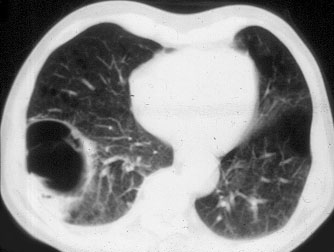

The preoperative work-up should always include clinical and functional evaluation (arterial blood gas analysis and pulmonary function tests with plethysmography), chest x-ray (Figure 6), computed tomography (Figure 7), and V/Q scan (Figure 8). Pulmonary angiography (Figure 9) has been reported to show some advantages in evaluating the underlying lung; however, it is not routinely performed.